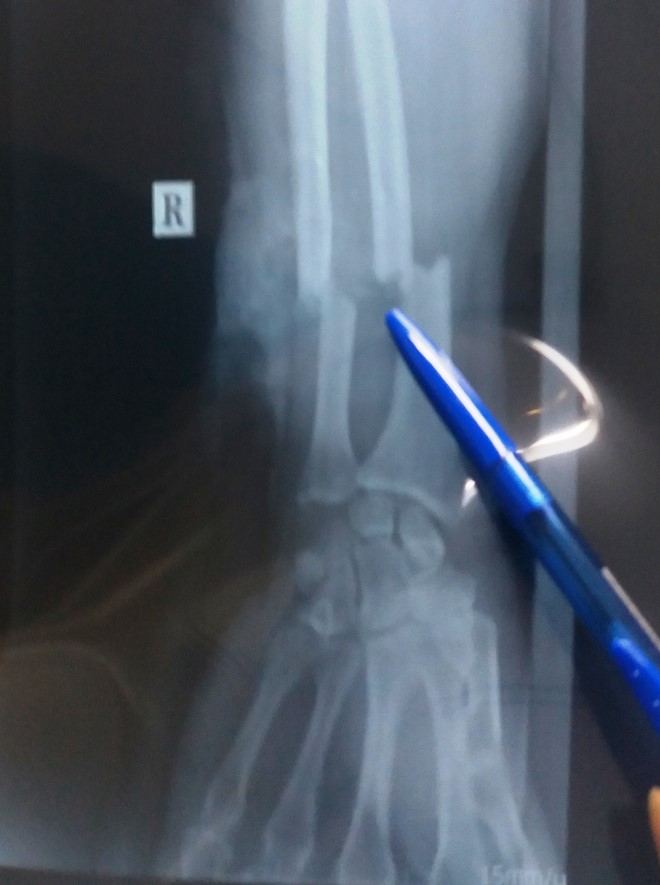

Nạn nhân sau đó được đưa đi cấp cứu trong tình trạng bị chém gần đứt lìa cẳng tay phải, lộ xương bánh chè gối trái, đứt bán phần cơ rộng đùi trái.

Hình chụp X quang xương tay phải của nạn nhân. Ảnh: Tri thức trực tuyến. |

Bác sĩ Nguyễn Hồng Hà, đại diện lãnh đạo BV Nhân dân Gia Định thông tin, sau hơn 6 giờ thực hiện ca mổ với ê kíp 10 người, nạn nhân cơ bản đã qua cơn nguy kịch, tỉnh táo.

Hiện ông B. được chăm sóc trong phòng vô trùng, theo dõi tuần hoàn nuôi dưỡng, chức năng cổ, bàn và ngón tay.